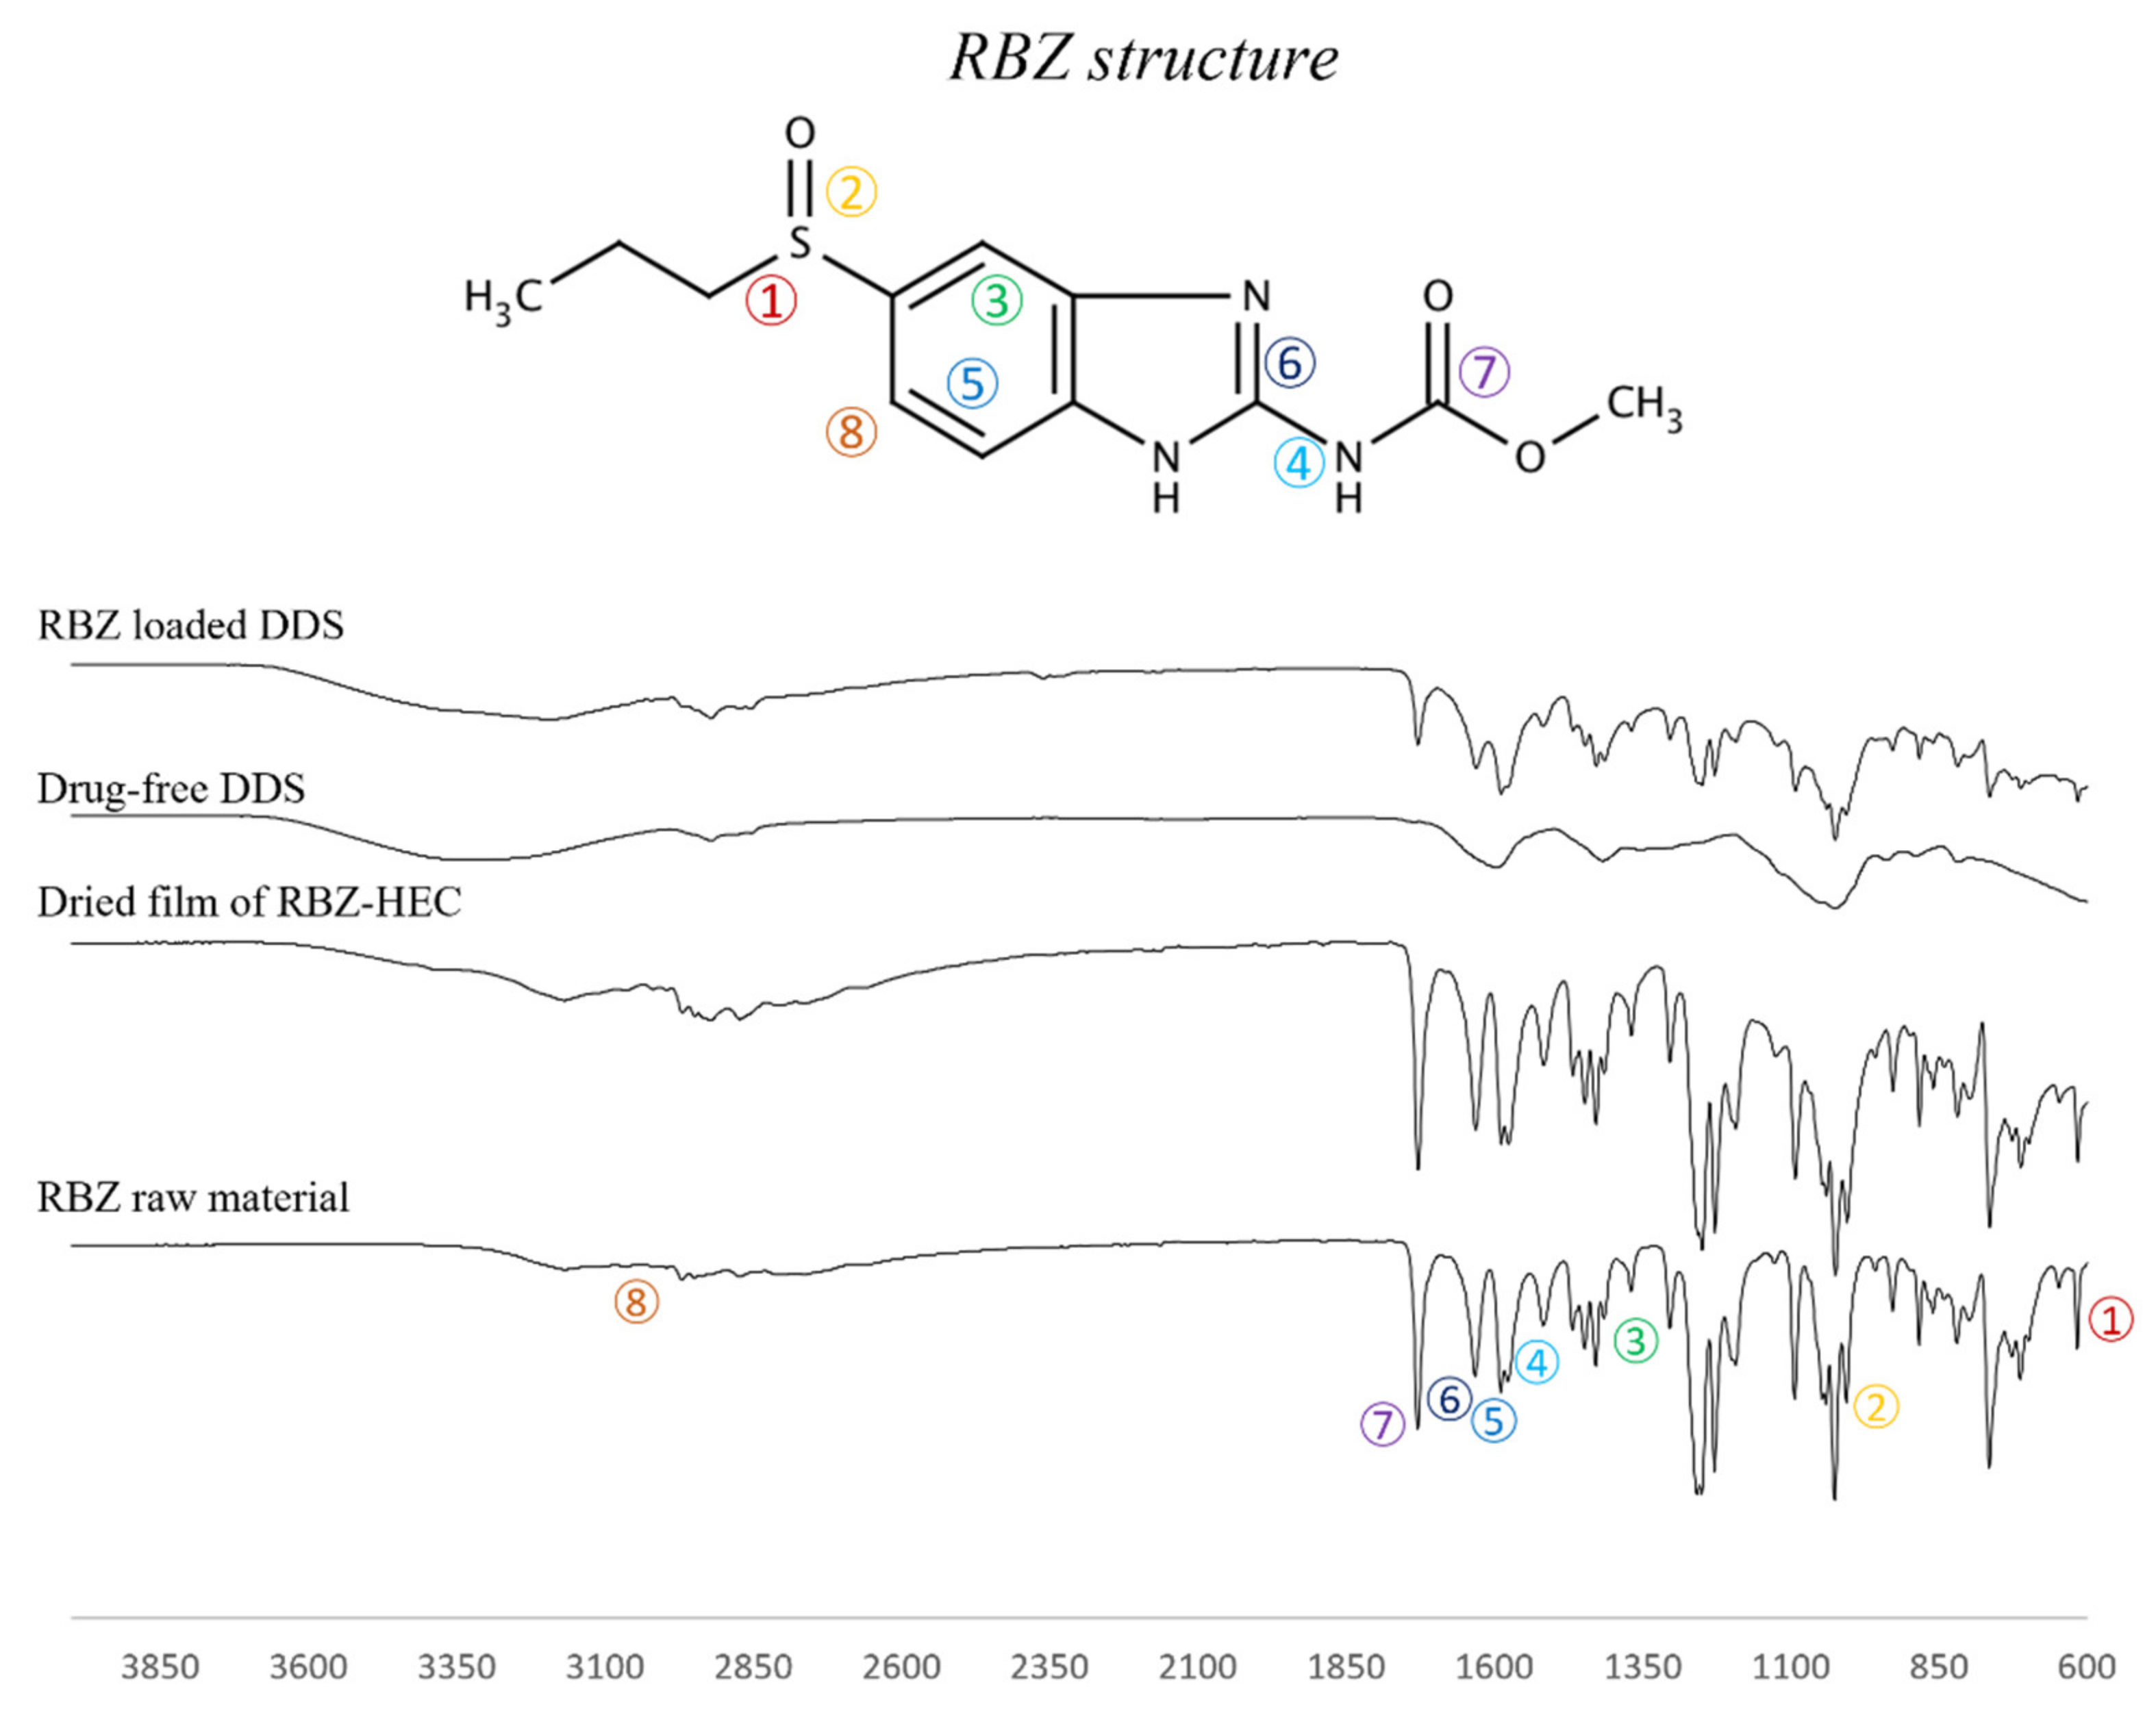

2.4. FT-IR and DSC Analysis

4.2.5. FT-IR Analysis